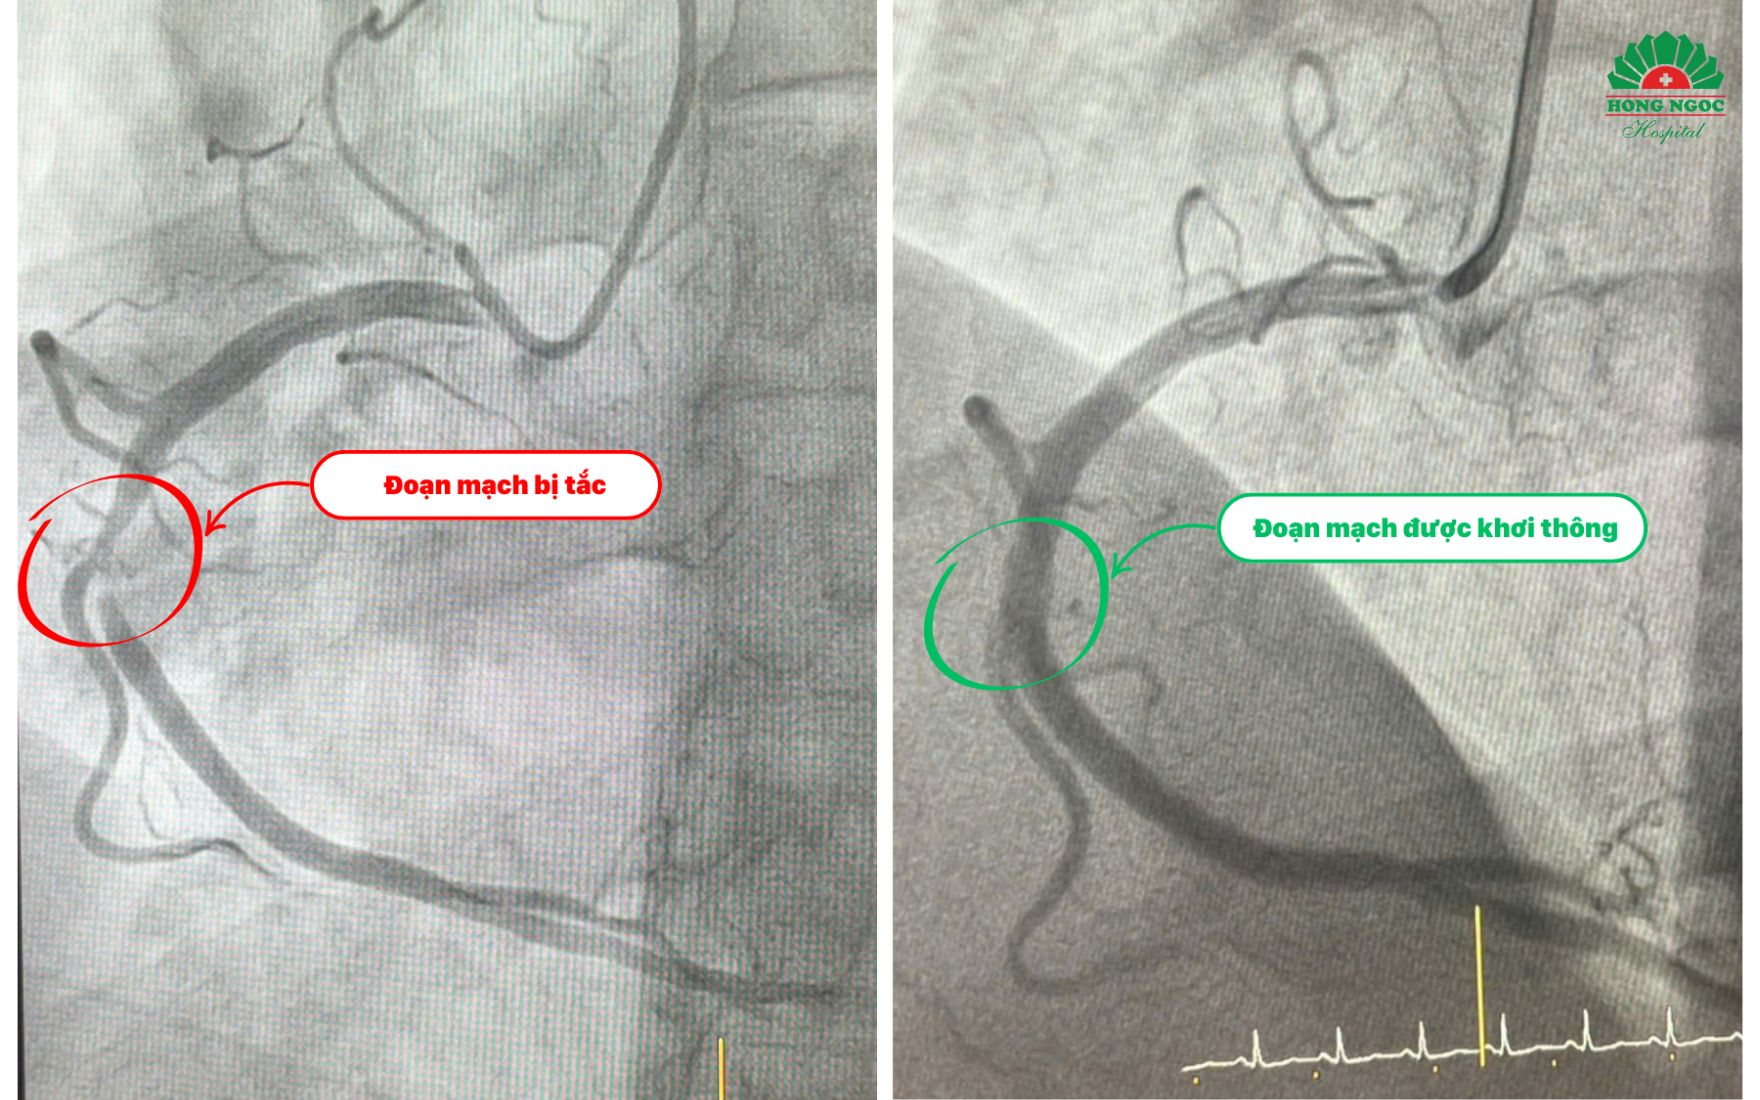

Nhận thấy tình trạng nguy cấp, các bác sĩ nhanh chóng kích hoạt quy trình cấp cứu nhồi máu cơ tim. Bệnh nhân được chụp động mạch vành bằng hệ thống DSA hiện đại, qua đó phát hiện đoạn II của động mạch vành phải - một trong những mạch máu chính nuôi tim bị hẹp nặng. Để khơi thông dòng chảy và cứu tim khỏi tổn thương, các bác sĩ đã quyết định đặt một stent vào vị trí bị tắc nghẽn.

Tuy nhiên, một thách thức bất ngờ đã xảy ra: khi thực hiện can thiệp qua động mạch cánh tay, bệnh nhân gặp phải tình trạng co thắt mạnh, khiến việc đặt stent trở nên khó khăn. Với sự nhạy bén và kinh nghiệm dày dặn, ê kíp bác sĩ nhanh chóng chuyển sang can thiệp qua động mạch quay trái và thành công khơi thông dòng chảy, giúp bệnh nhân thoát khỏi nguy kịch trong gang tấc. Không chỉ vậy, các bác sĩ còn áp dụng kỹ thuật bảo vệ nhánh nuôi thất phải, đảm bảo dòng máu được tái lưu thông hiệu quả, nâng cao được hiệu quả sau can thiệp.

Hình ảnh mạch vành của bệnh nhân trước và sau can thiệp đặt stent